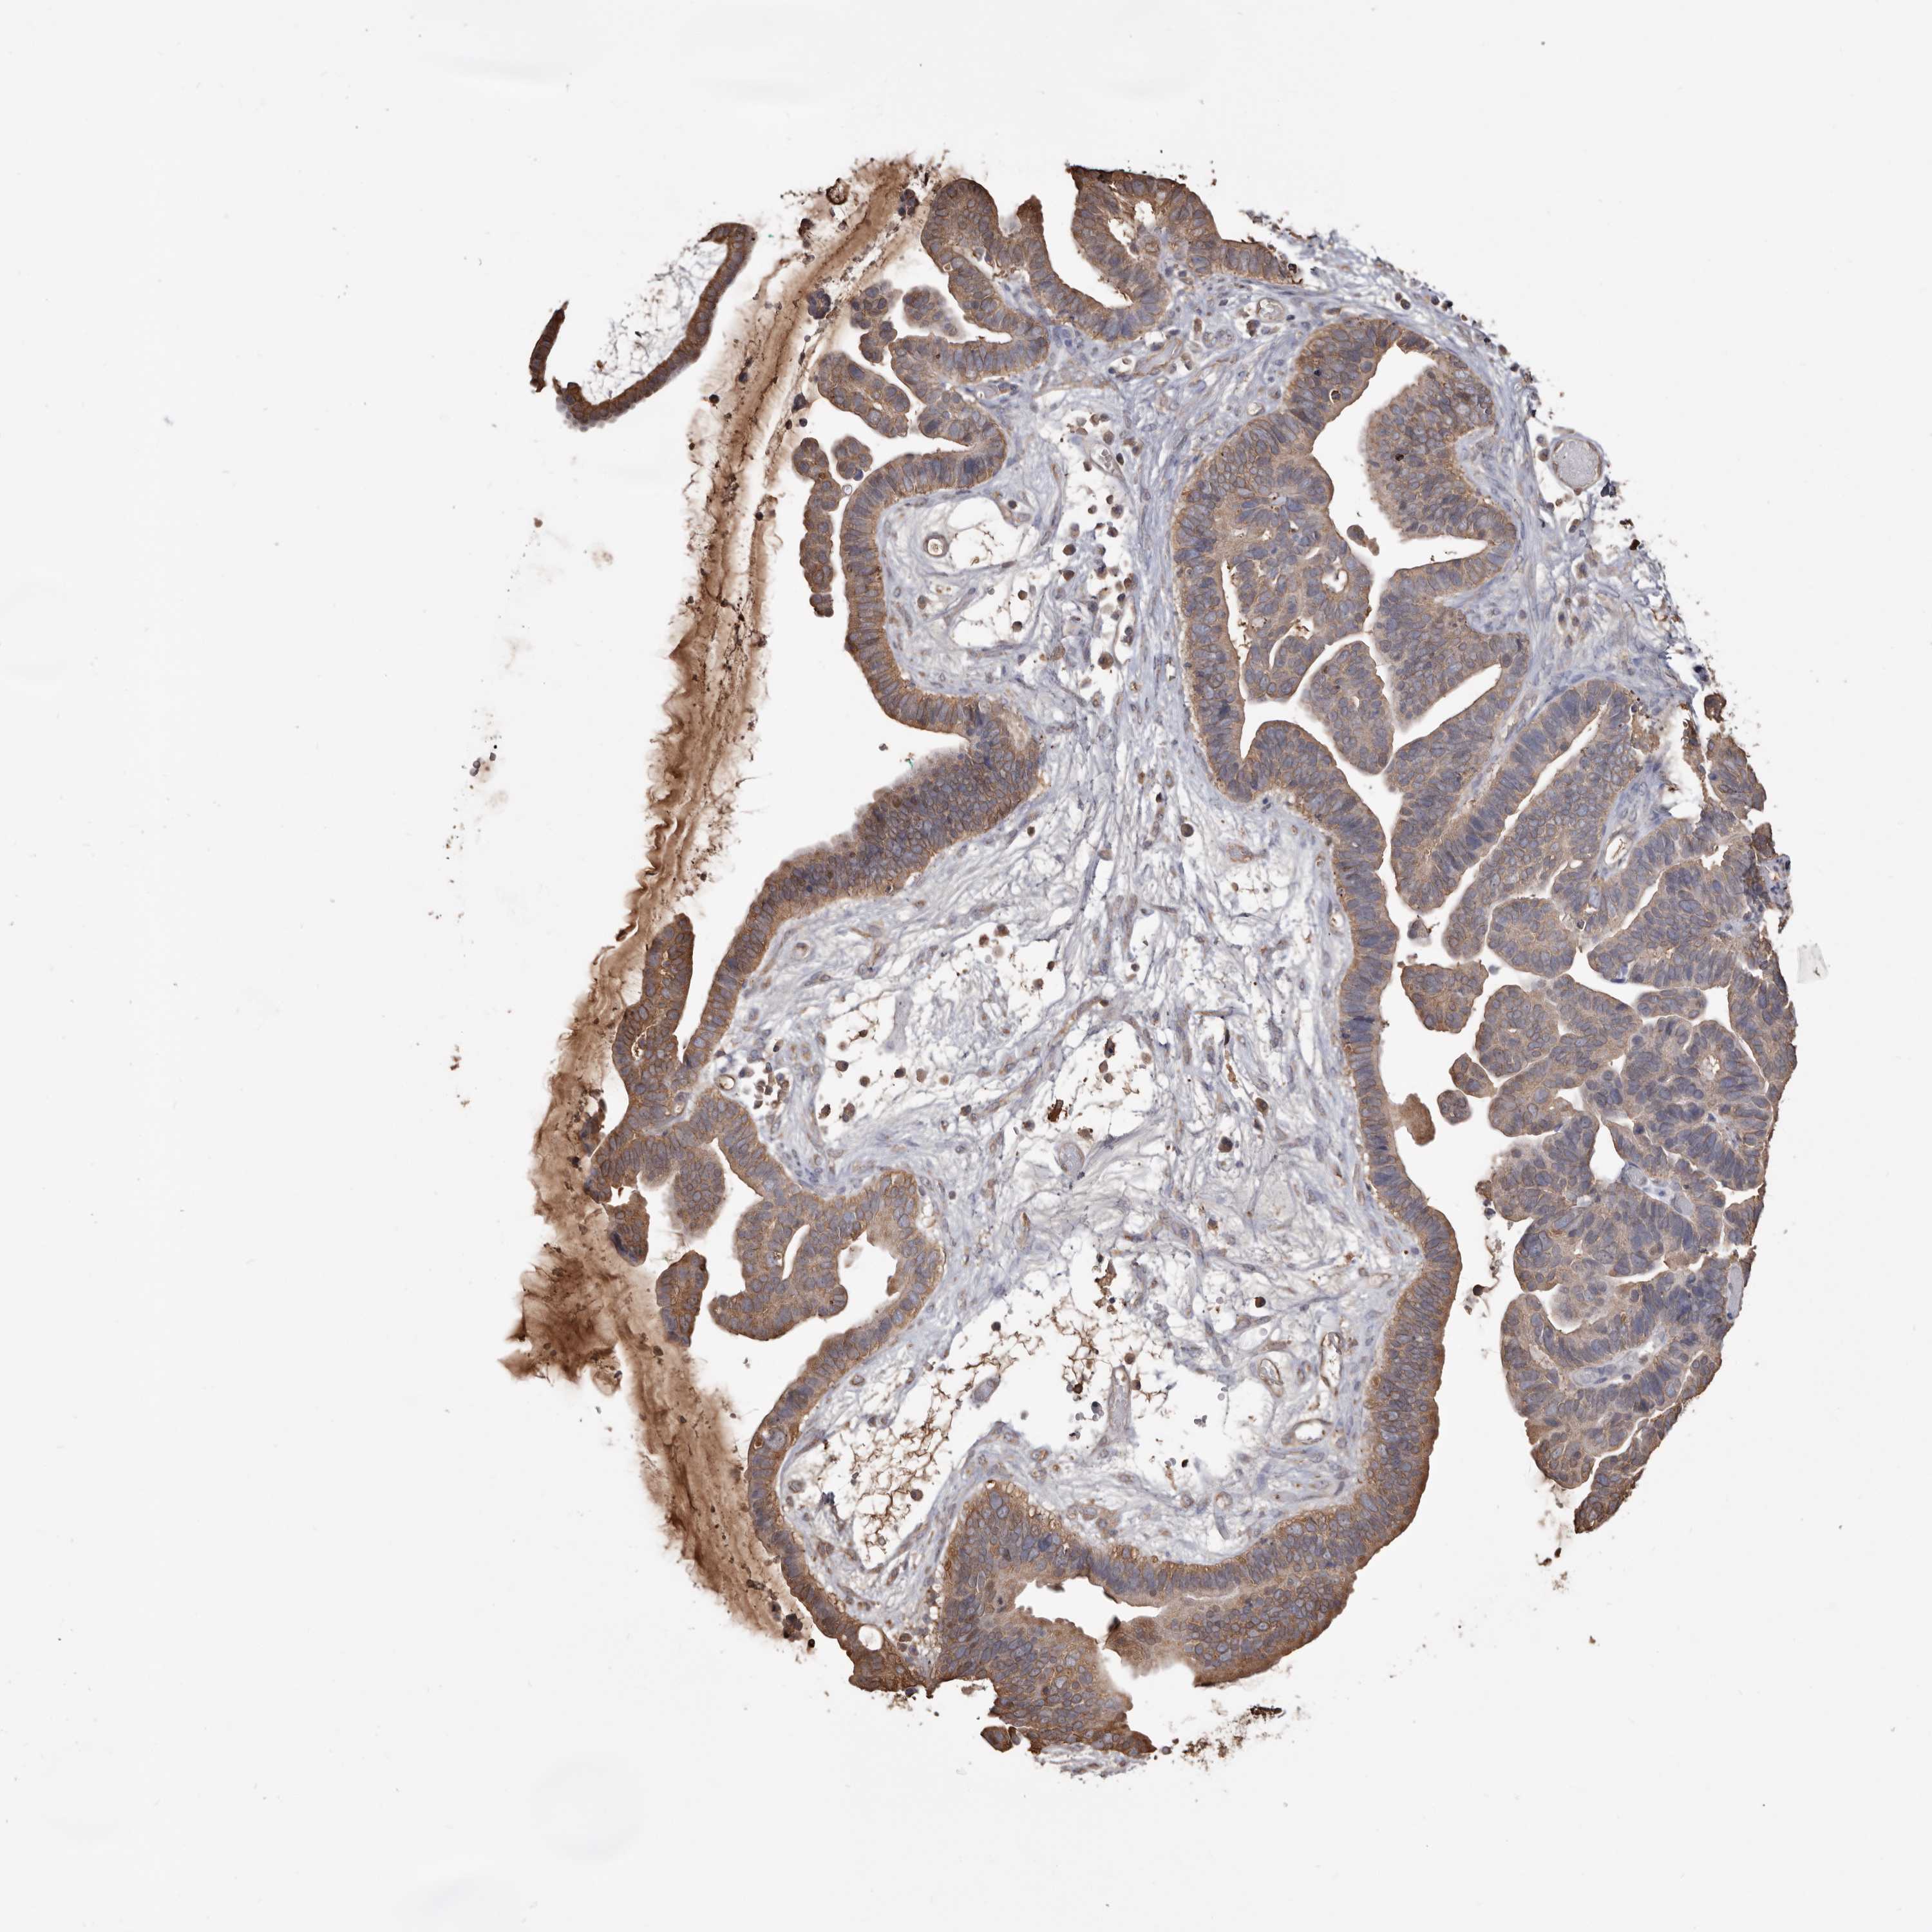

OVARIAN CANCER - Protein expressioni

A mouse-over function shows sample information and annotation data. Click on an image to view it in a full screen mode. Samples can be filtered based on level of antibody staining by selecting one or several of the following categories: high, medium, low and not detected. The assay and annotation is described here.

Note that samples used for immunohistochemistry by the Human Protein Atlas do not correspond to samples in the TCGA dataset.

Antibody stainingi

Antibody staining in the annotated cell types in the current human tissue is reported as not detected, low, medium, or high, based on conventional immunohistochemistry profiling in selected tissues. This score is based on the combination of the staining intensity and fraction of stained cells.

Each image is clickable and will lead to virtual microscopy that enables deeper exploration of all samples and also displays staining intensity scores, fraction scores and subcellular localization as well as patient and tissue information for each sample.

Antibody HPA029501

Antibody CAB019421

Staining

High

Medium

Low

Not detected

Intensity

Strong

Moderate

Weak

Negative

Quantity

>75%

75%-25%

<25%

None

Location

Nuclear

Cytoplasmic/membranous

Cytoplasmic/membranous,nuclear

Cystadenocarcinoma, serous, NOS

Carcinoma, endometroid

Cystadenocarcinoma, mucinous, NOS

Carcinoma, NOS